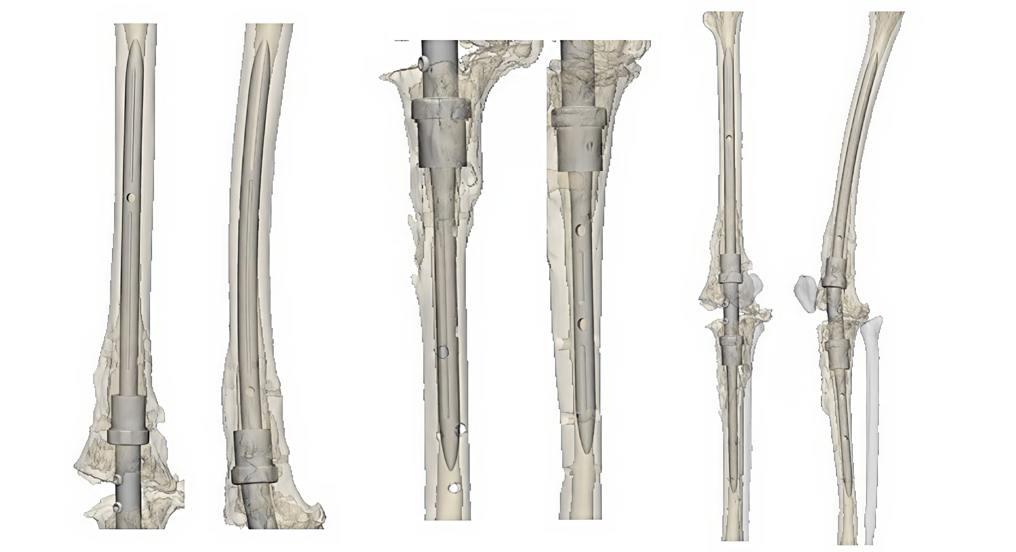

Anterior and lateral views showing how the customized implant would fit in patient's leg with top half of leg, bottom half of leg, and entire leg

These illustrations from Onkos Surgical show the anterior and lateral views of the customized implant. The first pair of images shows how the device fits in the top half of the leg, the second pair shows the bottom half of the leg, and the third pair shows a full view of the implant.

In a typical knee fusion (arthrodesis), we place a metal rod inside the bones from the top of the hip to the ankle, creating stability. The rod is usually one piece, and the smallest rods are around 12 millimeters wide (0.4 inches). We would then access the patient’s leg from the hip and guide the rod down the leg bones to the ankle.

But because of this patient’s size, we would have had to go through several inches of tissue to access her hip bone, extending the surgery and increasing the risk of complications. The leg bones are wider at the ends and narrow in the middle – even the smallest off-the-shelf rod would not have been able to fit inside her bones and support her weight. The knee area, where the femur and tibia would eventually connect, is both the narrowest place and the spot that absorbs the most weight-bearing stress.

She needed a wider rod to hold her weight, but it had to be narrow enough to fit inside her small bones. In our brainstorming session, we envisioned a two-piece rod that could be inserted lower in the leg and fortified in the middle upon insertion.

The engineers tapered the ends of each piece and designed them to overlap at the knee area, creating a larger, sturdier surface area called a lap joint. The overlap bulked the rod in the middle – its strength quadrupled with each extra millimeter of width. The engineers also designed a 3D-printed implant to aid fusion of the femur and tibia.